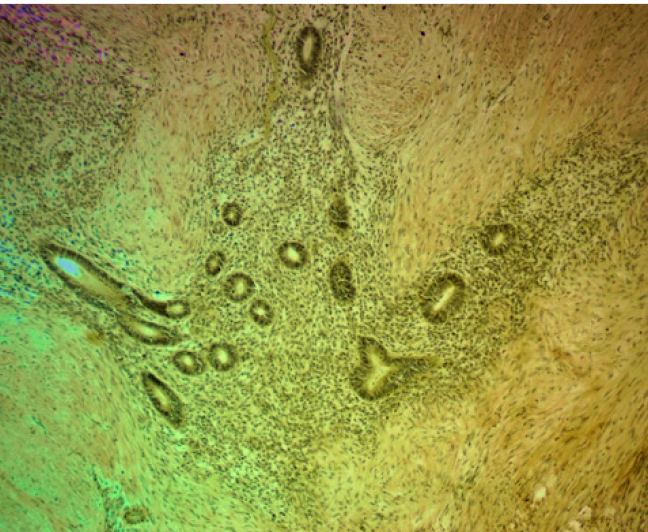

При гистологическом исследовании операционного материала во всех наблюдениях, независимо от органной локализации, патологический процесс характеризовался типовой для эндометриоза гистологической картиной: сочетанием желез, выстланных однорядным эпителием эндометриального типа с эндометриальной цитогенной стромой, вариабельной частотой кровоизлияний, отложением гемосидерина. Эндометриоидные гетеротопии имели преимущественно эпителиально-стромальное строение, очаги стромального эндометриоза встречались редко. В большинстве наблюдений эндометриоидные гетеротопии были множественными, размеры их варьировали от 1 до 2 полей зрения при луповом увеличении микроскопа. Эпителиальный и стромальный компоненты эндометриоидных гетеротопий характеризовались разнообразием морфофункциональных проявлений в виде пролиферации, секреции, кистозной трансформации желез с атрофией и/или десквамацией эпителия, подобно изменениям в эутопическом эндометрии в зависимости от фазы менструального цикла. Особенности и варианты морфофункциональных изменений в гетеротопиях зависели от органной локализации процесса. Для эндометриоза передней брюшной стенки характерной была выраженная тенденция к кистозной трансформации эндометриальных желез с атрофией и/или десквамацией эпителиальной выстилки. При поражении различных отделов кишечника в очагах эндометриоза обнаруживали преимущественно пролиферативные изменения в эпителиальном и стромальном компонентах гетеротопий. Независимо от органной локализации заболевания, в цитогенной строме очагов эндометриоза и в окружающих их тканях была обнаружена лимфо-макрофагальная инфильтрация различной степени выраженности, наибольшая − в местах отложения гемосидерина. В некоторых случаях выявлялась очаговая лимфо-макрофагальная инфильтрация по типу микроабсцессов. В таких инфильтратах встречались гигантские многоядерные клетки, присущие продуктивному воспалению и гранулемам инородных тел. Вокруг очагов эндометриоза и между ними было обнаружено разрастание «полей» соединительной ткани с большим количество коллагеновых волокон. Такая особенность в большей степени была присуща эндометриозу передней брюшной стенки, промежности и легкого (рис. 1, 2). При эндометриозе различных отделов кишечника площадь пролиферации соединительнотканных волокон вокруг гетеротопий была значительно меньше.

Очаговая экспрессия α-SMA была обнаружена в цитогенной строме очагов экстрагенитального эндометриоза в концентрических пролифератах миофибробластов по типу микроскопических лейомиом. В мышечном слое кишки наблюдалась положительная экспрессия α-SMA, которая повторяла ход мышечных волокон, деформируя стенку кишки в местах локализации очагов эндометриоза (рис. 4).